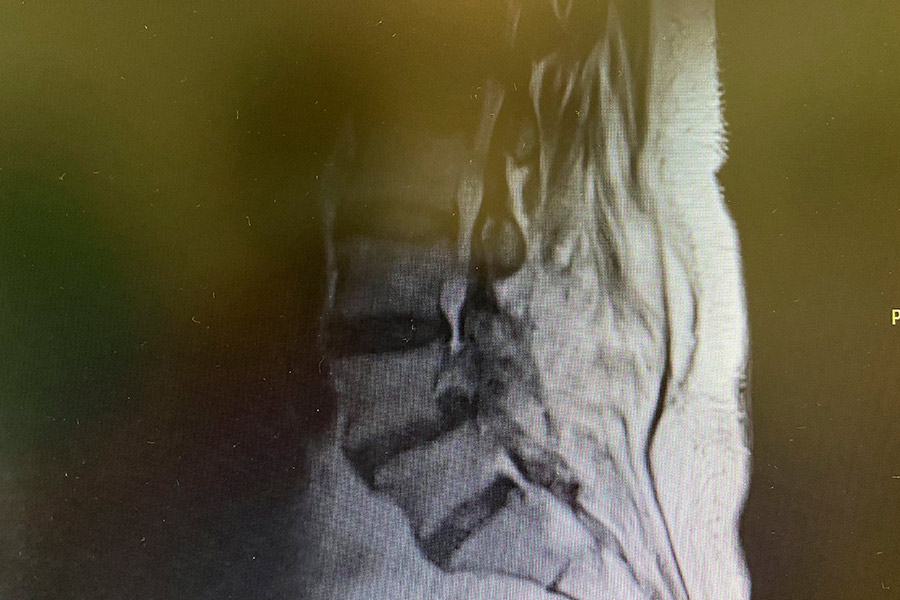

Hernia-discal-foramidal-josefa-carro-post

Tras finalizar la operación, de unos 45 min de duración, el Doctor Elgeadi consigue liberar el foramen en la zona donde se encontraba la hernia, por lo que la raíz nerviosa ya no se encuentra comprimida.

Dada la anterior operación, la paciente tenía varias cicatrices que se han tenido que esquivar, dificultando la operación. Se ha aplicado también un tratamiento de láser, eliminando así la sensibilidad dolorosa que sufría en las articulaciones posteriores.

La paciente podrá marcharse a su casa en la misma tarde, tras no mostrar dolencia y estar completamente recuperada de la operación unas horas después.